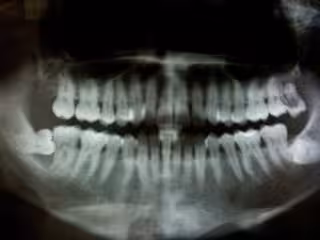

Periodontitis

FLICKR/FELIX E. GUERRERO